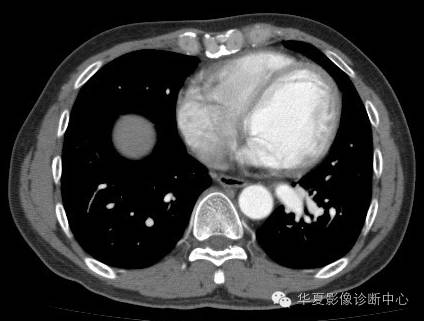

| 影像表现及分析: | 影像表现:定位左下叶;左下叶体积缩小,整体密度增高,支气管分布正常,其内见血管增多,但是走形正常,未见杂乱、迂曲的血管影;血管连向肺门下方软组织密度结节灶,结节与主动脉分界不清,增强后,见降主动脉发出异常粗大血管供血整个左下叶,左下肺动脉细小。 |

| 确诊依据: | CTA明确左下叶供血动脉为降主动脉发出 |

异常体动脉供应正常下肺基底段完整含义为起源于降主动脉的异常动脉供应下肺基底段,而基底段支气管树和肺实质正常,同时基底段肺动脉缺如或狭窄【大部分缺如(完全型),部分狭窄(不完全型)】;95%以上累及左下肺,因此也称为异常体动脉供应正常左下肺基底段。 病因尚未明确,可能是胚胎发育时期供应肺芽的背主动脉原始小分支退化不全,与肺实质形成异常连接,并影响肺动脉与肺血管床连接而导致此部位肺动脉发育不良,而支气管、肺组织的发育未受影响。本病的病理生理基础为左向左的分流,体动脉供应的肺组织充血,体循环的高压可增加肺血管床的压力和左心负荷,同时也增加肺循环量和压力而增加右心负荷,导致各种临床症群。本病可无临床症状,部分患者可有咯血、呼吸道感染、呼吸困难、充血性心力衰竭。 影像表现:左肺下叶体积缩小,整体密度稍增高,支气管树走形、分布正常,血管增多、稍增粗;增强后显示左下肺动脉幼小,甚至不发育;下叶由主动脉发出的粗大血管供血。 |